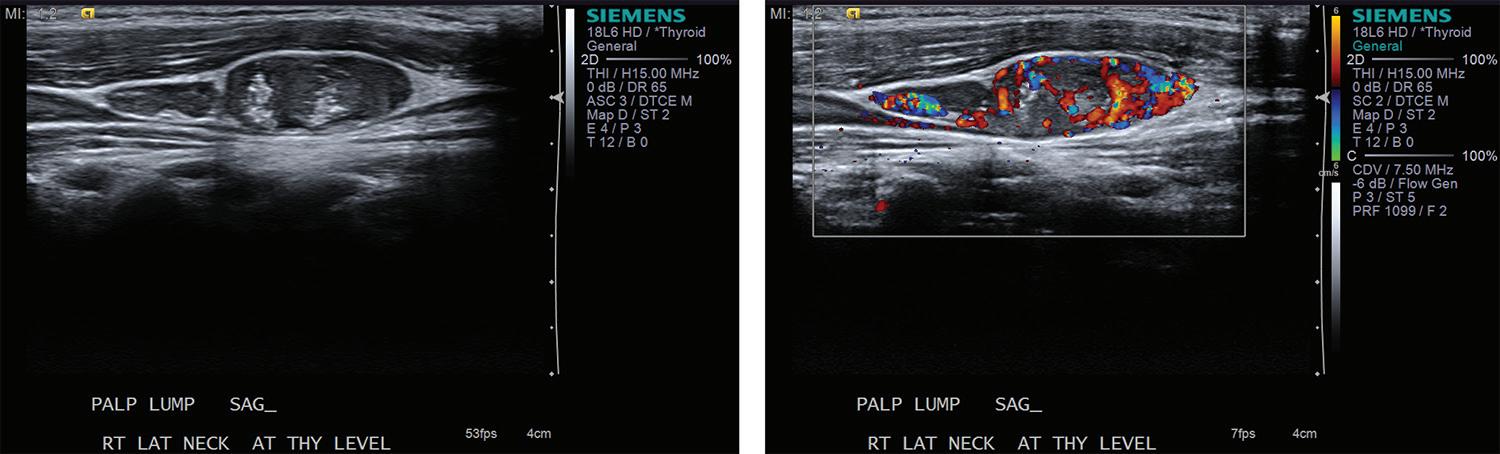

Volume 97, Number 1-2 www.entjournal.com 31 ORIGINAL ARTICLE

Additionally, diagnosis of lymph node invasion on presentation also serves as an important prognostic indicator for locoregional recurrence after the initial surgery.10,11

Approximately 30% of patients may develop recurrence following resection of primary disease, which is often associated with increased morbidity and mortality.12-14 PTC most often recurs or persists in cervical lymph nodes; therefore post-thyroidectomy surveillance with sonography of the neck and measurement of serum thyrogobulin level is required in the first 6 to 15 months and at regular intervals thereafter. The frequency with which patients are evaluated depends on serum thyroglobulin level and other risk factors.9

In evaluating recurrent disease, US findings have a reported sensitivity of 90%, specificity of 79%, and accuracy of 87.9%.8 The propensity of PTC for lymphatic spread and its effect on management of the disease underscores the need for accurate evaluation of cervical lymph nodes before and after thyroidectomy.

Elastography is a novel imaging modality that can be used clinically to assess elasticity of soft tissues. Elasticity is a parameter based on the strain or deformation of tissue in response to a physical force. Most malignancies reliably exhibit reduced elasticity and increased stiffness due to the nature of neoplastic growth, making this procedure a promising new development in the diagnosis of cancerous and metastatic foci.

The elastrography technique involves applying a force on the tissue and subsequently imaging the resultant deformation. This technique initially required the operator to physically push the transducer into the tissue to be examined, now termed quasi-static imaging. The unintended variable with

this technique was the differences in the degree of pressure applied by each observer. In efforts to increase objectivity and reproducibility, the acoustic radiation force impulse (ARFI) technique was developed, which involves emitting acoustic pulses inside tissue to generate micron-scale displacement.15

The distortion of tissues can be observed by ultrasonographic imaging, and areas of decreased strain can be recorded, creating a map of elasticity, known as an elastogram (figures 3 and 4). Additionally, whereas deformation can provide qualitative indications of tissue stiffness, measuring the speed of the shear wave, which is the speed with which the tissue wave travels perpendicularly from the pulse, can provide quantitative measurements of higher clinical value.16

Newer ARFI models can be used to measure shear wave velocity, which is inversely proportional to tissue elasticity, providing a means of numerical data collection.17 Supersonic shear imaging (SSI) or shear wave elastography (SWE) combines the technology of an applied ultrasonographic beam with ultrafast US imaging to create real-time, quantitative maps of tissue stiffness.18 Many newer models of US machines now have ARFI and/or SSI/SWE-based capabilities.

Review of literature